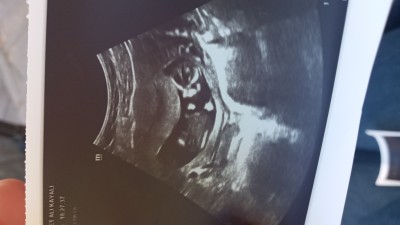

imagedoktorum erkeğe benziyor ama kesin biswy diyemem dedi

Gebelik haftası 14

Bencede erkek kafa yapısına göre

Yaaa çıkıntılı mi sence canım doktor çıkıntılı dedi de

Banada erkek gibi geldi.

Yok canim erkek bebekte yumurtalik oluyo yaa dr lar 2 tane nokta gibi olurmus ordan da anliyolarmis. Sanki senin bebegin bacak arasinda sa 2 tane nokta var dikkatki bak sende gorursun yumurtalik onlar.